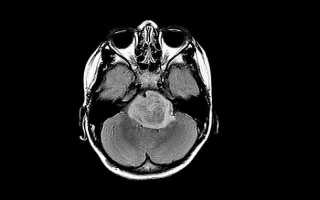

Выглядит глиома головного мозга как небольшая округлая или веретенообразная опухоль серовато-белого или темно-красного цвета диаметром от 2-3 миллиметров до размеров теннисного мяча. Растет это образование чаще медленно и характеризуется отсутствием метастазирования, но при этом развитие глиомы сопровождается дегенерацией окружающих тканей, что приводит к несоответствию размера опухоли и выраженности неврологического дефицита.

- МРТ (магнитно-резонансная томография) – один из самых информативных видов исследования. Выявляет локализацию и точный размер даже на ранних стадиях, так как предоставляет врачам картинку МРТ в трех измерениях. Метод не противопоказан во время беременности, в отличие от других видов диагностики;

- Магнитно-резонансная терапия. Это наиболее частый метод исследования, позволяющий получить контрастные изображения тканей мозга.

- МРТ. Процедура проводится практически во всех случаях, когда есть подозрения на мозговые патологии. Метод считается точным, потому как благодаря ему можно не только рассмотреть опухоль, но и уточнить её размер, место расположения и обнаружить процесс инфильтрации.